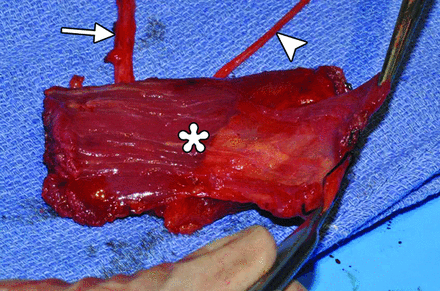

Free gracilis transfer is an effective method of smile rehabilitation for facial paralysis in selected patients (Fig 7).11⇓⇓–14 The gracilis muscle is harvested from the thigh with its neurovascular supply (Fig 8). The graft is then inset in the plane deep to the superficial musculoaponeurotic system and extends from the zygomatic arch to the modiolus of the oral commissure (Fig 9). The vascular pedicle of the graft is typically anastomosed to the facial artery and vein, and the obturator nerve can be anastomosed to a cross–face nerve graft and/or the masseteric branch of the trigeminal nerve.15,16 Vascular ring coupler devices are often used for the venous anastomosis.17 Depending on the particular type, the ring coupler may appear as a hyperattenuated circular structure overlying the angle of the mandible (Fig 10). Postoperative flap monitoring by physical examination alone is challenging and is often supplemented with use of a hand-held Doppler probe. Color Doppler sonography is an effective and noninvasive tool for evaluating arterial and venous flow through the pedicle of the buried free flap, whereby a sharp systolic upstroke should be evident in the artery and continuous flow should be observed in the vein (Fig 11). The examination can potentially avoid wound exploration to verify appropriate muscle perfusion and is typically performed on the first postoperative day.18 The arterial waveform of the graft should normally demonstrate a sharp systolic upstroke, while the vein may normally exhibit a continuous waveform and should be compressible, except at the site of the ring connector device. A good functional outcome correlates with normal muscle structure of the free flap depicted on MR imaging.19 Imaging may also be useful for measuring the graft thickness,20 which potentially relates to function.

Gracilis free flap. Intraoperative photograph shows the harvested flap (asterisk) with an attached vascular pedicle (arrow) and nerve (arrowhead).